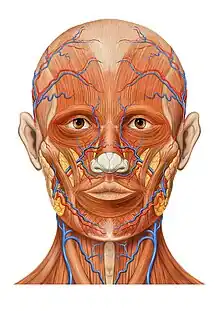

Muscles et vaisseaux de la face

Coupe sagittale Muscles et innervation faciales